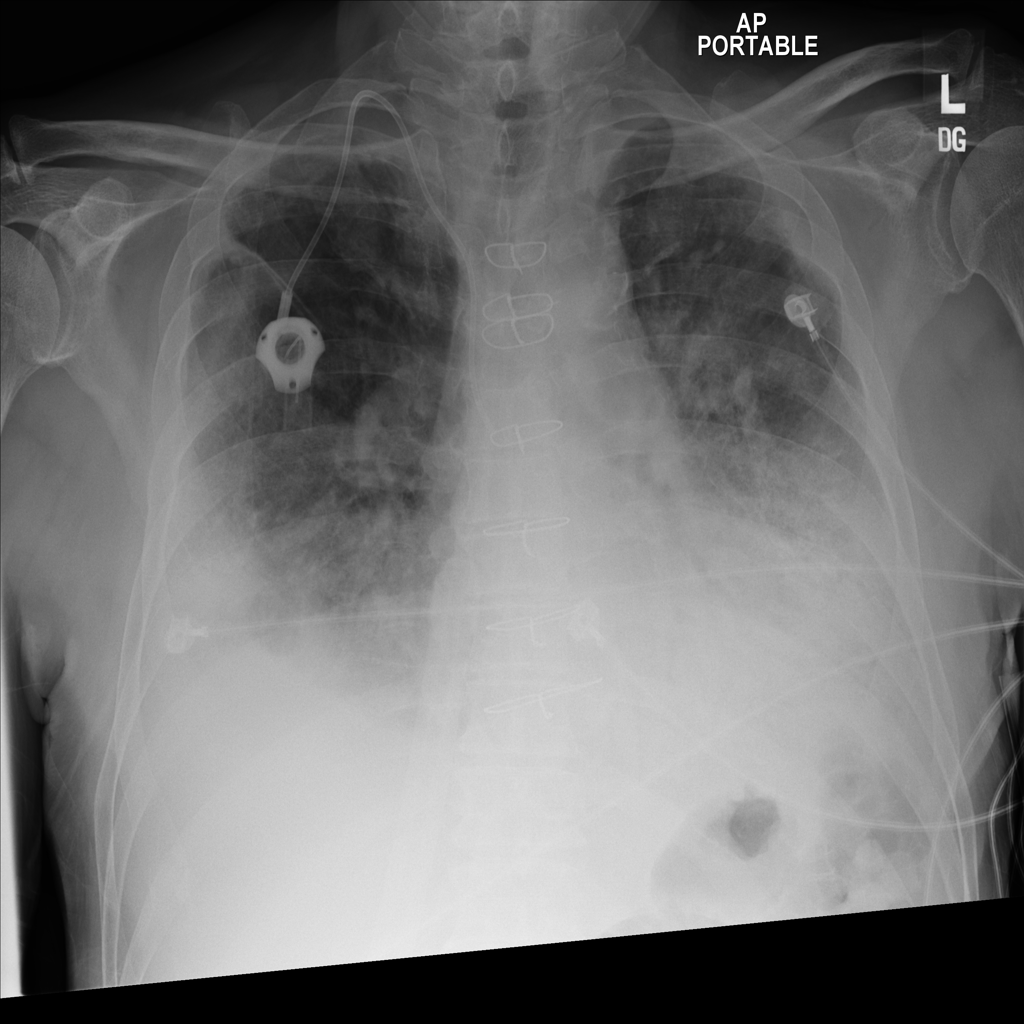

PAT-C0E5 · IMG-002Effusion

PAT-C0E5 · IMG-002

PA